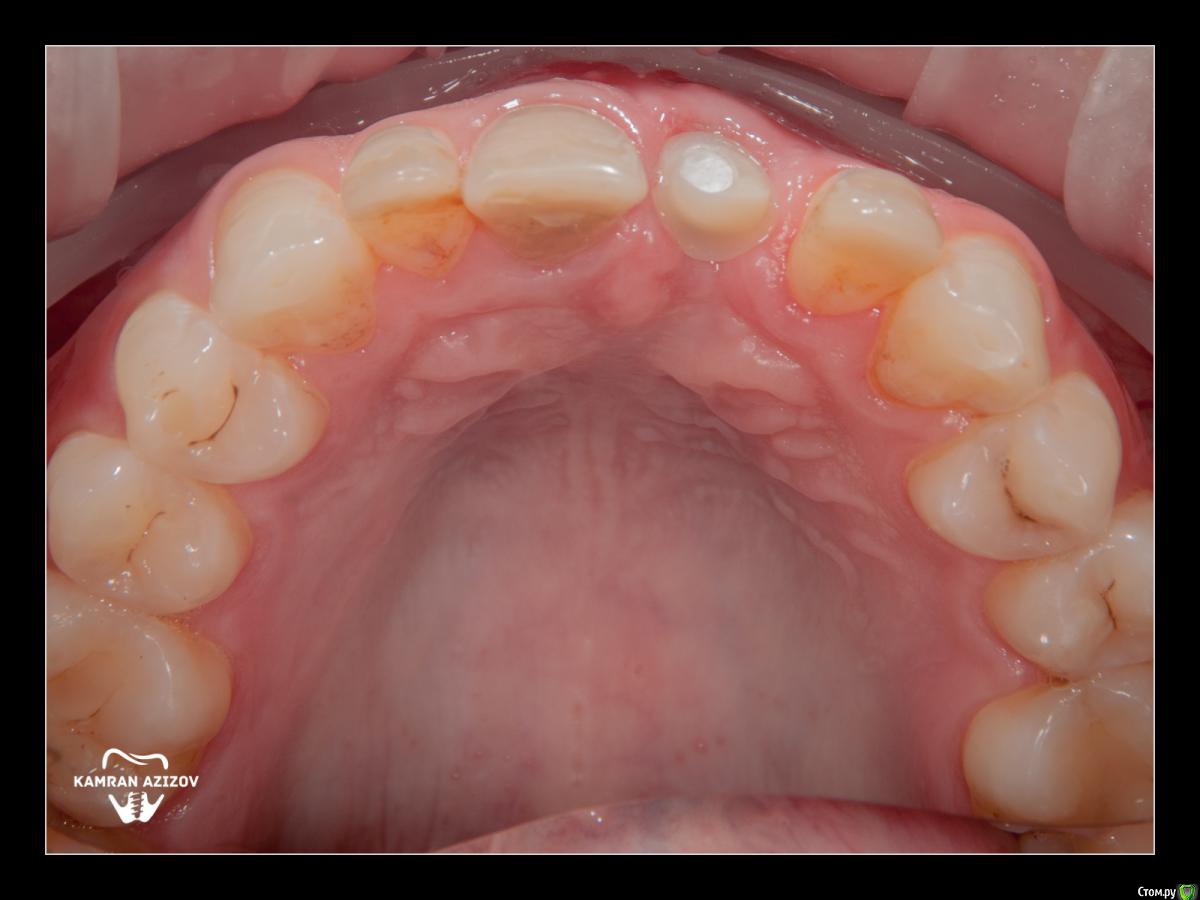

kamranchick Опубликовано 8 октября, 2019 Поделиться Опубликовано 8 октября, 2019 удаление зуба+консервация лунки с вестибулярным ССТчерез 2 месяца имплантация с фдм по карлоссучерез 4 месяца замена на более длинный фдм и широкийпостоянная коронка 5 Ссылка на комментарий